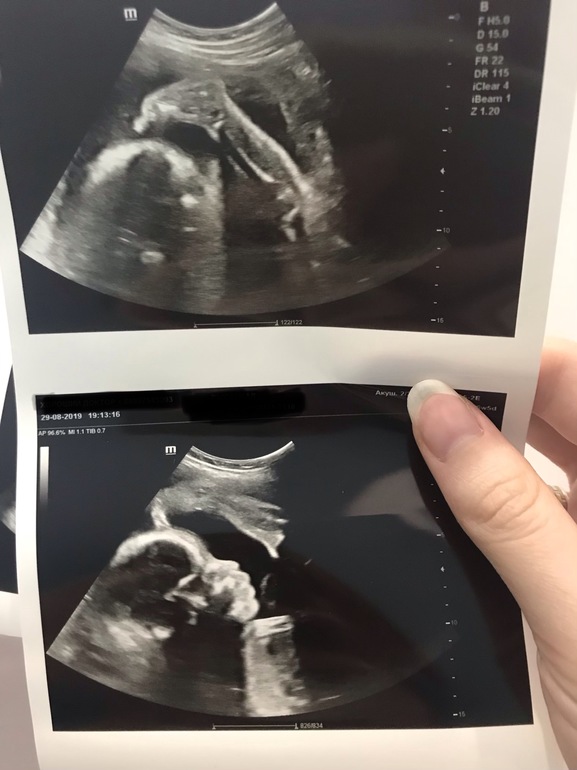

Контрольное УЗИ и ягодичное предлежание

Второй триместрПрекрасное узи, замечательный наш малыш с хорошими показателями и такой смешной 🙈 зевает, ножкой голову чешет, хмурится, отворачивается 🥰

Благополучно сидит на попе - чисто ягодичное предлежание на 27 неделе.

Наш замечательный малыш❤️: